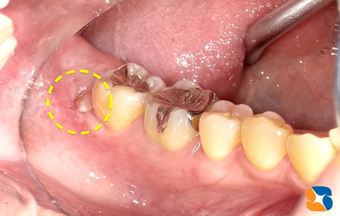

抜歯後の穴には、痛みを抑え、傷口を早く回復させるテルプラグ(=無料)を挿入して、糸縫いを行いました。今度は、左(向かって右)の親知らず(横向きで骨の中に完全に埋まっている)を抜歯するとのこと。次回も共にがんばりましょう!